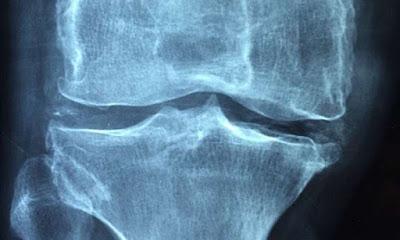

Sin embargo, la prueba clave para una posible nueva terapia es su capacidad para atacar el proceso de reparación natural que se ve comprometido por la edad o una enfermedad inflamatoria. Los investigadores demostraron que administrar PEPITEM adicional limita la pérdida ósea y mejora la densidad ósea en modelos animales de menopausia, que es un desencadenante común de la pérdida ósea osteoporótica en humanos. Sus estudios también mostraron hallazgos similares en modelos de enfermedad ósea inflamatoria (artritis), donde PEPITEM redujo significativamente el daño y la erosión ósea.

Estos hallazgos fueron subrayados por estudios que utilizaron tejido óseo humano, extraído de pacientes mayores durante una cirugía articular. Estos estudios demostraron que las células de personas mayores responden a PEPITEM, aumentando significativamente la maduración de los osteoblastos y su capacidad para producir y mineralizar tejidos óseos.